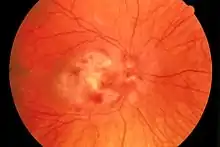

| Fundus photograph of CMV retinitis | |

Cytomegalovirus retinitis, also known as CMV retinitis, is an inflammation of the retina of the eye that can lead to blindness.[1] Caused by human cytomegalovirus, it occurs predominantly in people whose immune system has been compromised, 15-40% of those with AIDS.[3]

Those areas infected by cytomegalovirus have cells evolve to necrosis, though inflammation within the retina is not great. Rhegmatogenous retinal detachments can occur following the development of holes in areas of healed retinitis (retina may be atrophic).[11][12] Proliferative vitreoretinopathy has been observed in cases of retinal detachment.[13]